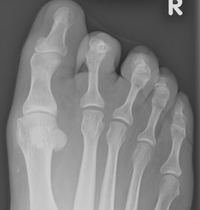

Krallenzehen vor der Operation

Der Knochen des Grundgliedes wird eingekürzt, so dass nach entsprechender Weichteilplastik die muskuläre Balance wiederhergestellt ist. Der Eingriff kann ohne Vollnarkose mit einem Fußblock durchgeführt werden.